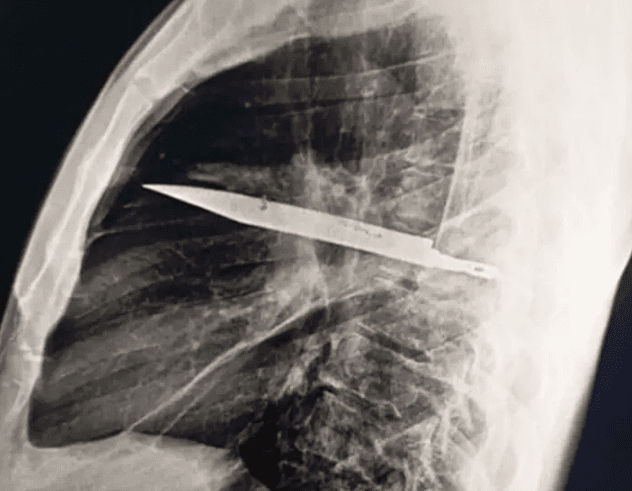

Um homem de 44 anos descobriu que carregava, sem saber, uma lâmina de faca alojada no peito havia oito anos. O caso, registrado na Tanzânia e publicado pela Biblioteca Nacional de Medicina dos Estados Unidos, chamou a atenção da comunidade médica pela ausência total de sintomas durante todo esse tempo.

A surpresa veio após o paciente procurar atendimento por conta de uma secreção anormal próxima ao mamilo. Sem dores, febre ou qualquer alteração nos sinais vitais, os médicos decidiram investigar com exames de imagem e a radiografia revelou a presença de uma faca atravessada em seu tórax, sem atingir órgãos vitais.

Segundo o Hospital Nacional de Muhimbili, o homem relatou que havia sido esfaqueado durante uma briga oito anos antes, sendo atingido no rosto, costas, abdômen e peito. Na época, recebeu atendimento médico, mas como não foram realizados exames de imagem, os profissionais apenas suturaram os ferimentos, sem perceber a presença da lâmina no corpo.

Após a descoberta, o paciente foi submetido a uma cirurgia para a retirada da faca e passou 24 horas na UTI. Em seguida, ficou mais dez dias internado para observação e se recuperou sem complicações.